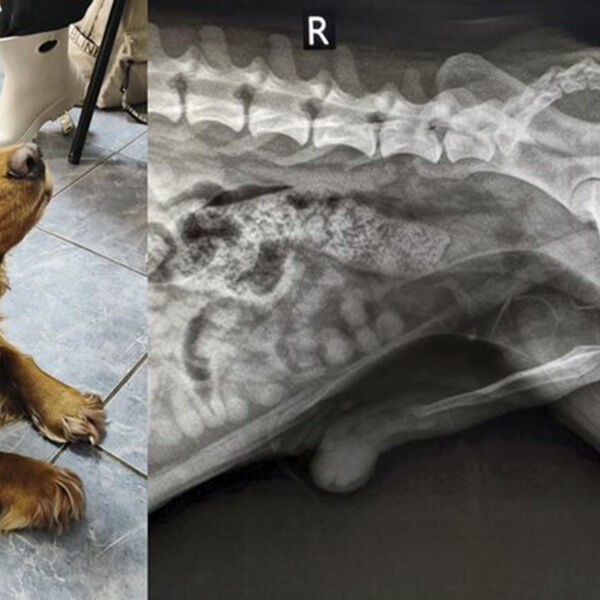

В ветклинике Коптево специалисты спасли собаку породы кокер-спаниель по кличке Вольт, которая проглотила швейную иглу. Об этом »Москве 24» рассказали в столичной госветслужбе.

«При осмотре терапевт Анна Кубатина заметила, что из заднего прохода Вольта торчит швейная нитка. Пациента срочно отправили на рентген», – добавили в пресс-службе.

Врачи установили, что за ниткой тянулась и игла, которая застряла в прямой кишке. Хирург Евгений Бахтин и анестезиолог Светлана Дорожкина провели операцию по извлечению иглы, после этого питомца отпустили домой.